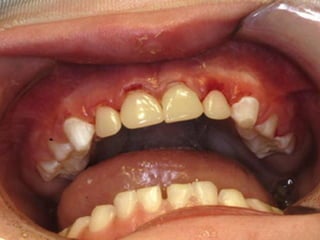

Con todas sus complicaciones

potenciales

Es más frecuente

en niños que se

quedan dormidos

con el biberón

Esto tiene un papel

biológico al provocar

la desmineralización

de los dientes